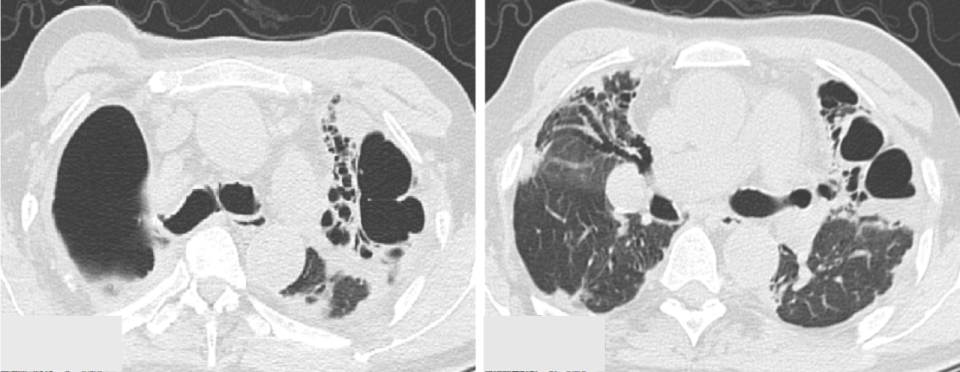

女性 55 岁,原有系统性红斑狼疮(SLE)史,长期口服甲泼尼龙 8 mg bid,因发热胸闷 1 周入院。入院查胸部 CT 示右下肺球状渗出实变影(图 1),较前新增。

图 1 2 个多月 CT 示左下肺条索影(A);本次入院 CT 示右下肺大片实变影伴少许晕征(B-C)

经患者存在免疫抑制(SLE长期口服激素),高热、气急伴低氧急性起病,影像学疑似曲霉感染,予伏立康唑经验性抗曲霉治疗,同时予美罗培南经验性抗菌治疗。

治疗 3 天后,患者仍有高热伴胸闷气急,血 GM(-)、曲霉特异性 IgG(-),不支持曲霉感染,遂予气管镜 BALF mNGS 检测。